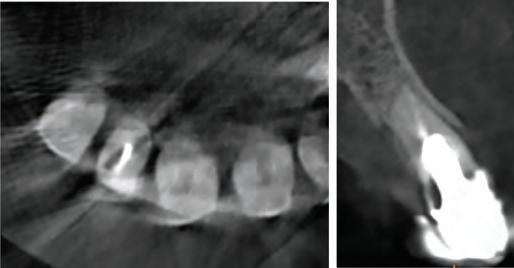

On clinical examination, UR1 was responsive to viability testing, and did not present periapical lesions on the radiograph performed on the same day (Figure 1). UR1 was discoloured and in a more palatal position than the contralateral central UL1 (Figure 2). The aesthetic analysis highlighted an asymmetry of the gingival zenith between UR1 and UL1. Through the use of a periodontal probe, after plexus anaesthesia, the altered passive eruption of the type IA junctional epithelium was confirmed according to the classification of Coslet et al. (Figure 3).

FIGURE 1: Radiograph without periapical lesion.